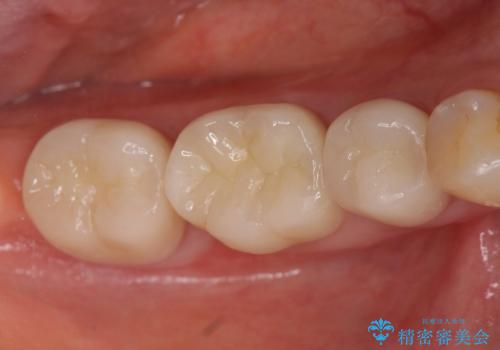

- 奥歯が欠けてしまったので診て欲しいといらっしゃった方の症例です。

再根管治療終了後、オールセラミッククラウンによる補綴を行いました。

今回用いたオールセラミッククラウンはジルコニアフレームという白い素材の上にセラミックを盛っているため、審美性が非常に高いのが特徴です。

また、ジルコニアは人工ダイヤモンドの材料にも使われているほど高い強度を持っており、そのためオールセラミッククラウンは審美性だけでなく、奥歯やブリッジの補綴も可能とするクラウンです。